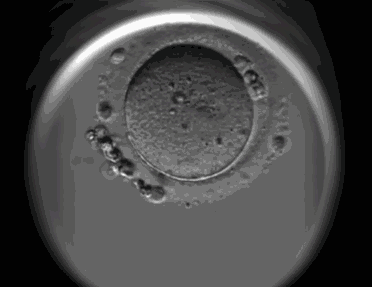

新生命的起点

文章图片

原理:生命在母体中最初的样子是什么样?这里显示的就是人类胚胎最早的发育阶段。精子和卵子的接触和融合,使得受精卵中出现了两个细胞核——雄原核和雌原核,两个原核融合后,快速的激发了受精卵的分裂。最初的两次分裂,使得受精卵形成了四个大小几乎一致的细胞,而第三次分裂,则不等的产生了四大、四小八个细胞——这最早决定了胚胎的方向。随着分裂的继续进行,一颗受精卵分裂为了数百个细胞组成的空心细胞团,即囊胚。而囊胚的进一步发育,则开启了最早的组织分化。